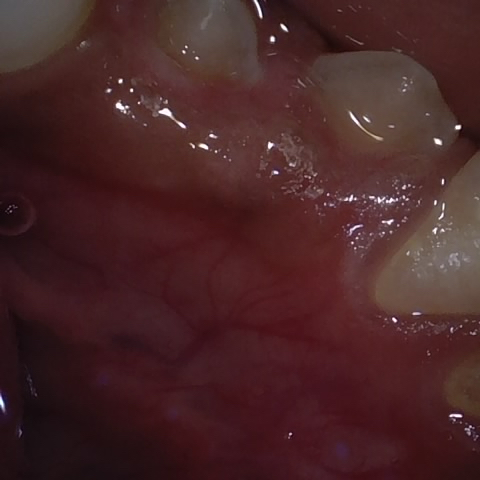

NHD25470

Annotated as "Good"